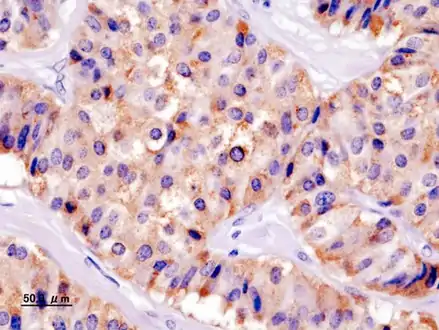

Chromogranin A

Insulin immunostain